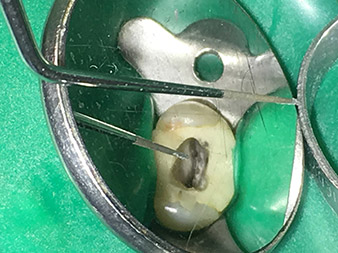

punta 3E

Retirada de limas para endodoncia rotas

La punta 3E está especialmente concebida para la retirada de limas para endodoncia rotas o partidas. Mi experiencia me ha demostrado que esto es posible en el área coronal hasta la sección central del canal si se dispone de un aumento óptico correspondiente (lupa con un factor de aumento de 3,6 o, mejor, un microscopio).

En este caso debe trabajarse con una punta no diamantada y muy puntiaguda, pues así es posible liberar los fragmentos de instrumentos rotos en el área de la dentina ayudándose de un microscopio. Además, el instrumento también resulta ideal a fin de liberar una lima para canal radicular rota en el área coronal para, a continuación, sacarla mediante vibración utilizando la punta 5E.